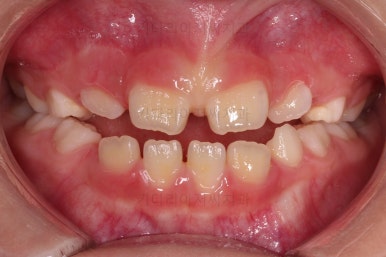

초진 시 입안의 모습입니다.

아래쪽 치열이 전반적으로 윗니보다 앞쪽에 위치한 전형적인 앵글씨 3급 부정교합인데요.

어금니에서부터 앞니까지 아랫니가 윗니보다 앞쪽에 위치하네요.

특히 앞니는 아랫니가 윗니보다 나와있는 "반대교합" 상태였고요.

또한 위아래로 겹침이 없고 떠있는 "개방교합" 상태였어요.

즉, 앵글씨 3급 부정교합 - 반대교합 - 개방교합 등 굉장히 복합적인 교합의 문제를 가진 환자였습니다.